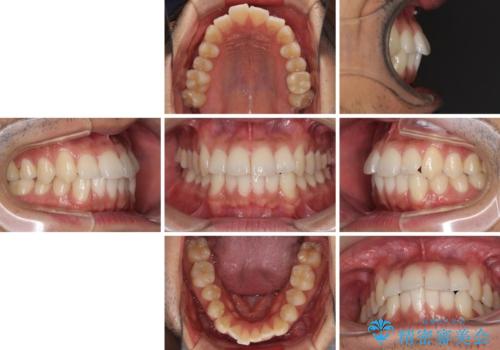

- 前歯のデコボコを治したいとのことで来院された患者様です。

上下顎ともに歯列全体の後方移動とIPR(歯と歯の間を削る)によってデコボコが解消するように設計し、インビザラインにより治療を行うこととしました。

毎日22時間以上しっかりとマウスピースを装着していただいたので、スムーズに治療が進みました。歯と歯の間を削ることでうまくスペースコントロールでき、1年強で終えることができました。